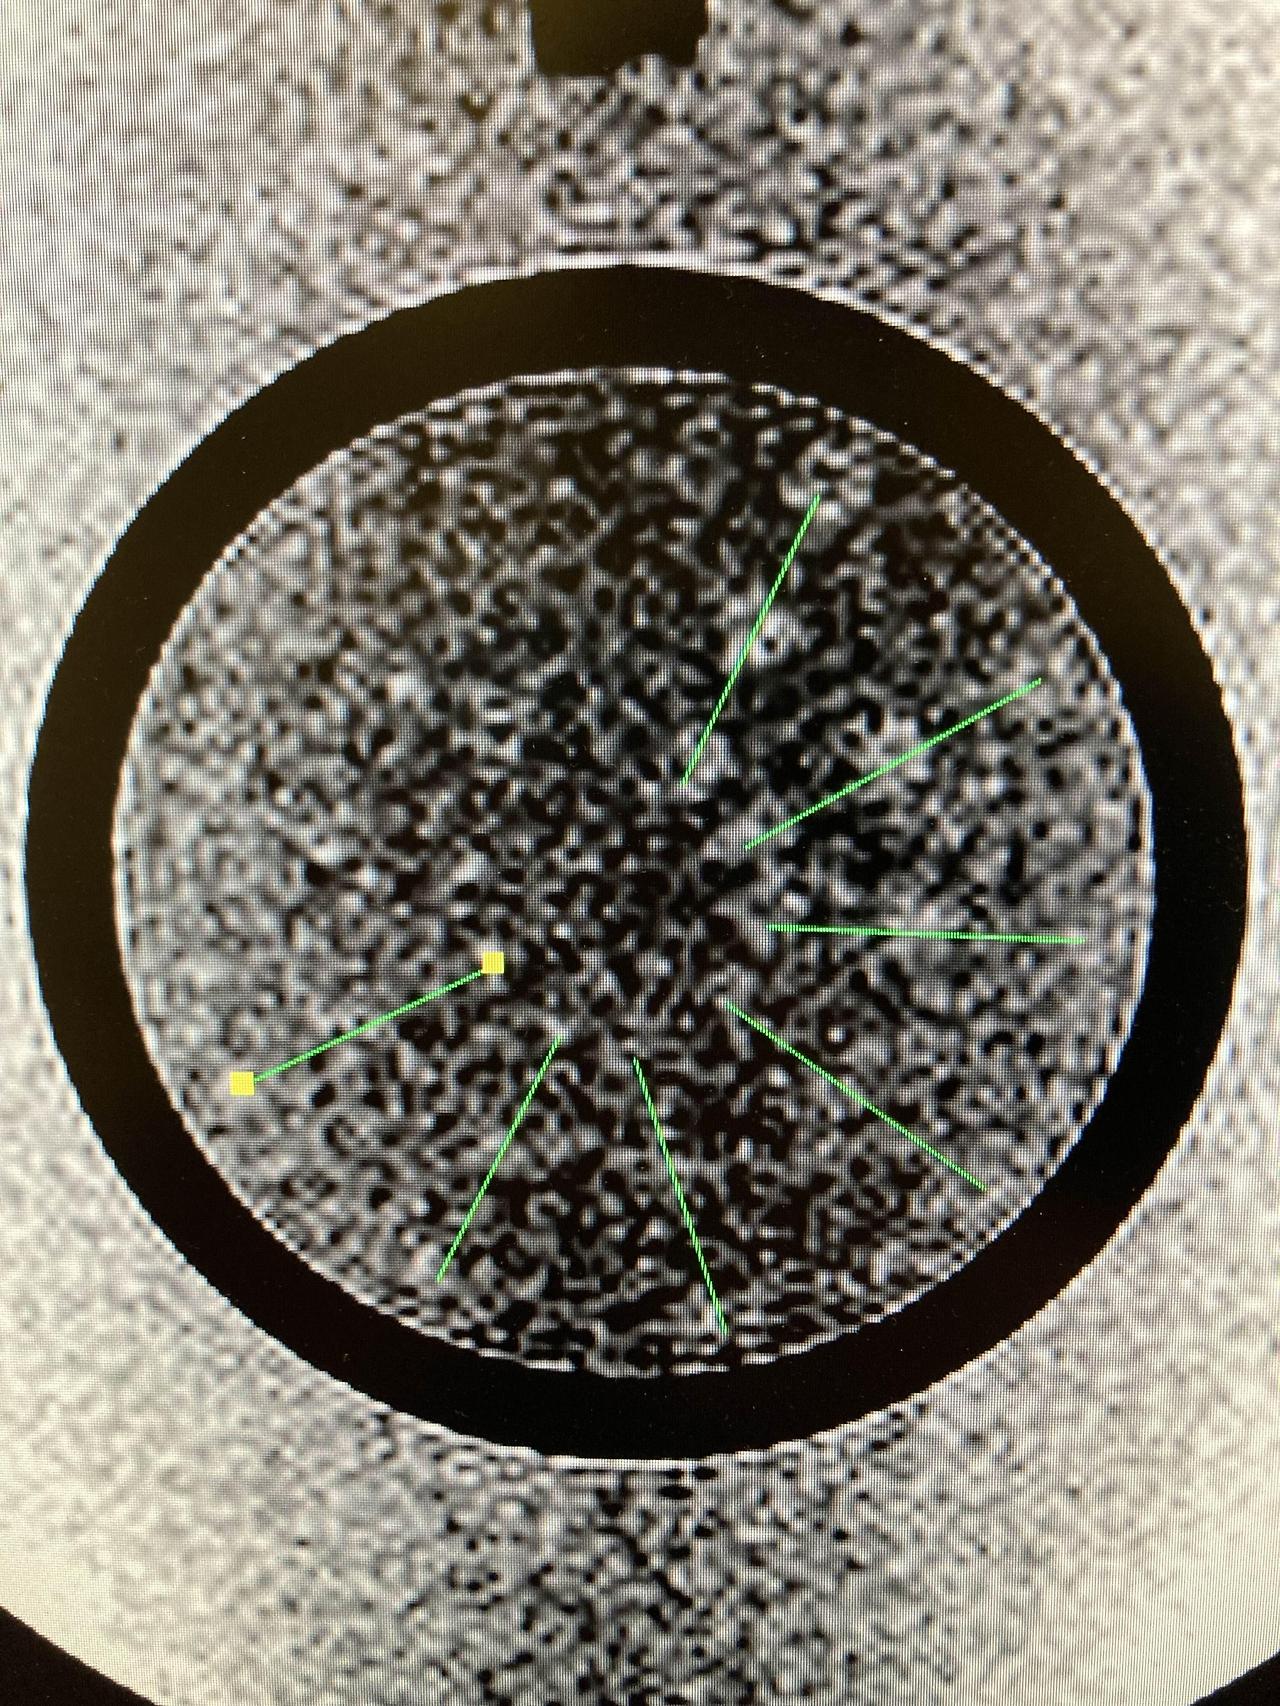

마지막으로 저 대조도 분해능, 저 대조도 분해능은 약한 자장의 장비에서는 흐리게 묘사될 수 있기 때문에 주의해야 하고 ACR 정도관리에서도 쉽게 Fail이나 지적사항이 나올 수 있는 부분으로 각별히 신경 써야 합니다. 가장 많이 Fail 하는 부분이기도 합니다.

가장 잘 보일 수 있는 WW WL을 조정한 후 부챗살 무늬로 표현되는 세 점을 모두 확인해야 저 대조도 분해능을 판단할 수 있습니다. 위의 그림에서는 7개 정도의 선이 구분 가능 하디고 판단할 수 있습니다. 오늘은 ACR phantom을 이용한 정도 관리 부분에 대해서 알아보았습니다.